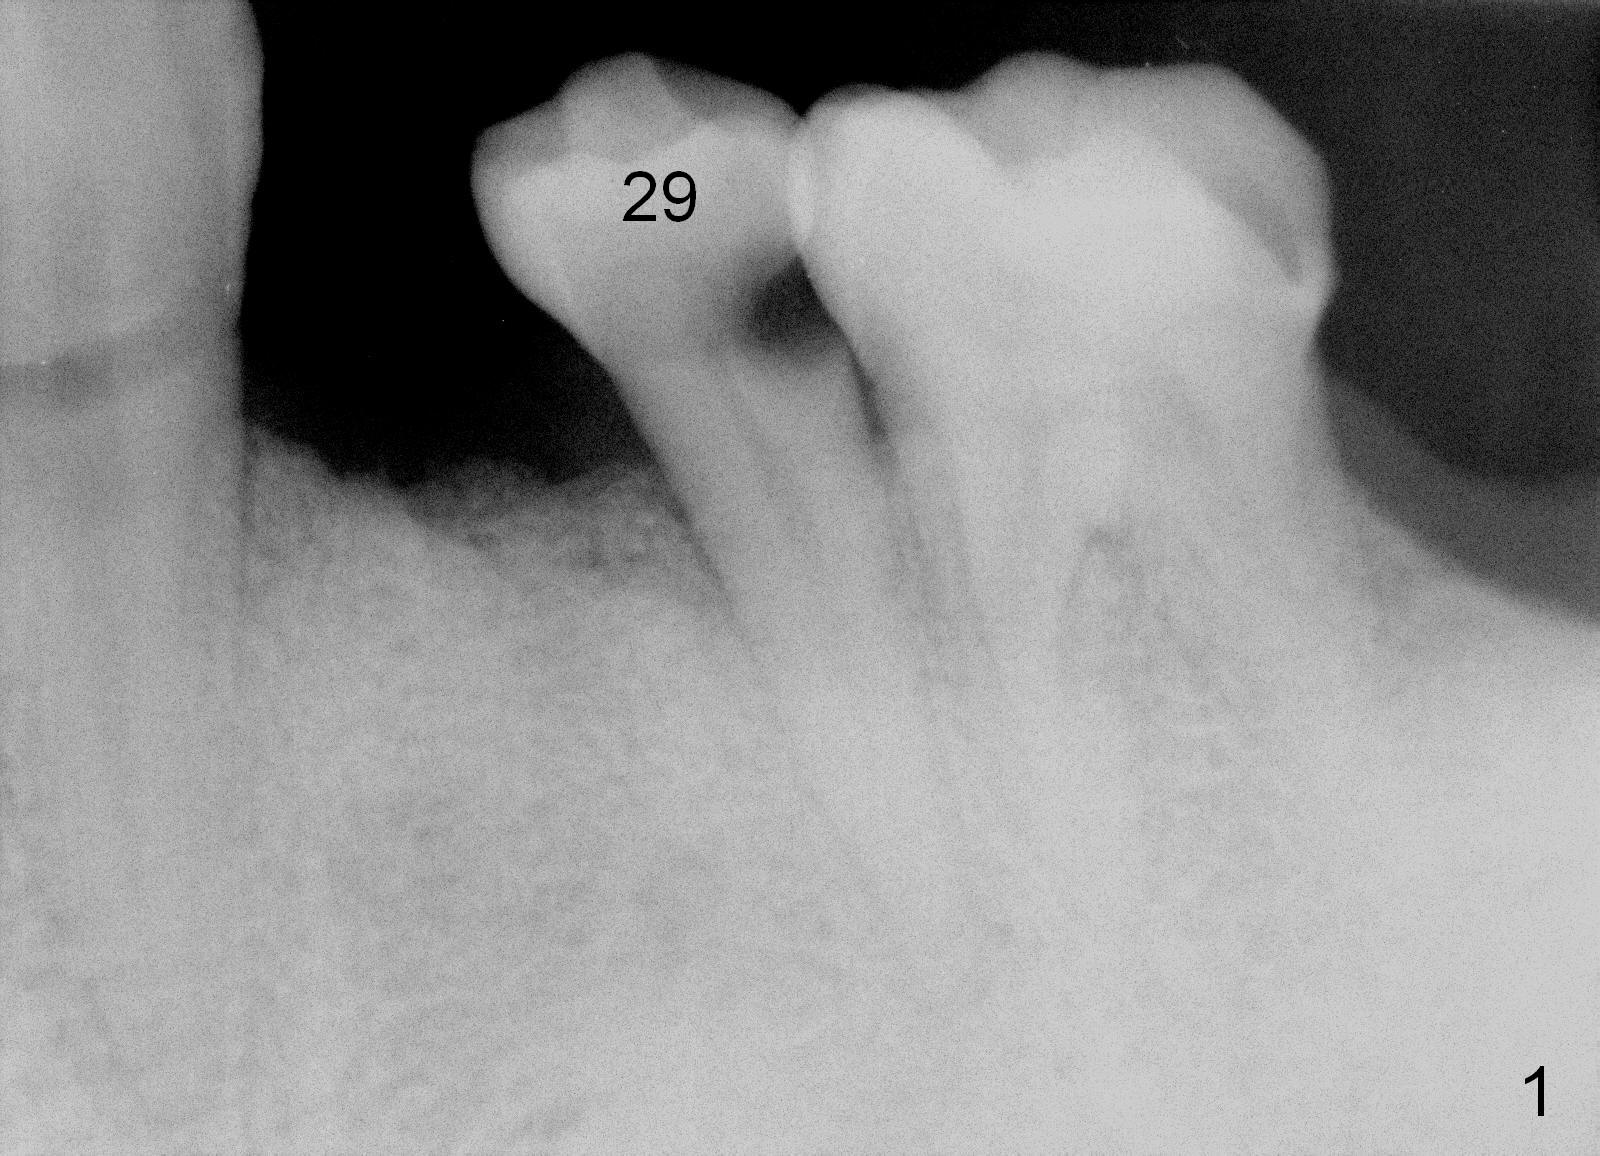

A 56-year-old man has poor dentition (Fig.1). The tooth #20 fractures (not shown) after root canal therapy (Fig.2). A 4.5x14 mm bone-level implant is planned (Fig.3).

CT sagittal section of a similar case shows that the root is also long, but curved (Fig.4). A 4.5x14 mm implant is slightly longer than the root. The apex of the implant has distance to the underlying nerve (N). The coronal section shows that the implant should be placed lingually (Fig.5 L), since the buccal (B) plate is thin (Fig.6 between arrowheads). The first drill (2 mm) is to be placed lingually (Fig.7 red arrow). When the implant is placed, there should be a buccal gap, to be filled with bone graft (Fig.5 red circles).

Take a PA prior to surgery to show the underlying nerve.